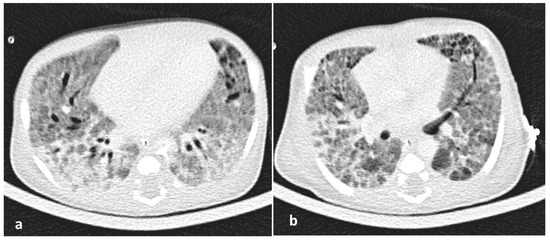

2. Case Report

3. Results